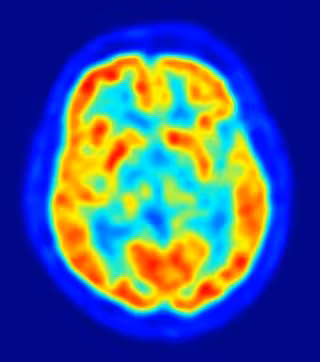

Investigadores de la Universidad de Wisconsin-Madison, en Estados Unidos, han descubierto que algunas células nerviosas en el cerebro de un individuo despierto pero privado de sueño pueden permanecer durante cortos periodos de tiempo 'fuera de servicio', en un estado similar al sueño, mientras que el resto del cerebro permanece despierto. Este hallazgo, publicado en el último número de 'Nature', podría explicar pequeños olvidos o descuidos cotidianos, como perder las llaves.

Hasta ahora, los científicos habían pensado que la privación de sueño afectaba generalmente al cerebro entero. Los electroencefalogramas (EEGs, por sus siglas en inglés) muestran patrones de ondas cerebrales típicas de dos estados diferentes: el de vigilia y sueño.

"Sabemos que, cuando estamos adormilados, cometemos errores, nuestra atención se descentra y se baja la guardia", dice Cirelli, quien asegura que su equipo "ha visto con EEGs que, incluso cuando se está despierto, se pueden experimentar periodos de 'micro sueño, la causa más probable de somnolencia al volante.

Para realizar este hallazgo, los investigadores de la Universidad de Wisconsin insertaron sondas en grupos específicos de neuronas en el cerebro de ratas que se comportaban libremente. Después, los animales fueron obligados a permanecer despiertos durante prolongados periodos de tiempo y las sondas mostraron áreas de 'sueño local', a pesar de que las ratas parecían estar despiertas y activas.

"Incluso cuando algunas neuronas se desconectaron, la medición general de EEG del cerebro indicaba vigilia en las ratas", dice Cirelli, quien afirma que, cuando se prolongó el periodo de vigilia de estos animales, "comenzaron a cometer errores".